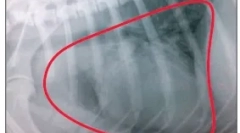

. Az orvos határozza meg a daganat méretét a keringés segítségével, majd egy bizonyos ideig figyelemmel kíséri növekedését. Ez további kutatást javasol. A vékony fecskendővel kiválasztott aspirát a tű bemenetét jelenti a sejtkiválasztás tömegére és a mikroszkóp alatt lévő következő vizsgálatukra. Az elemzés megerősítheti a zsírsejtek jelenlétét, amelyek a wen jele - egy jóindulatú tumor (lipoma). Ellenkező esetben az elemzési eredmények más sejtetípusok, például masculociták jelenlétét mutatják be a tumorban. A sebészeti biopsziát (a neoplazma teljes vagy részleges eltávolítását) általános érzéstelenítés alapján végzik. A szövet mikroszkópos vizsgálata lehetővé teszi a jelen lévő sejtek típusát. A tumor típusának becslése és más szervek állapota, a vérvizsgálat is szükség lehet, és további diagnosztikai vizsgálatok.